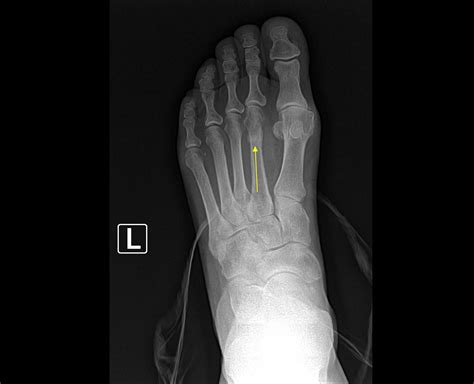

A hairline fracture, also known as a stress fracture, is a thin crack in the bone. In the case of a hairline fracture ankle, this crack typically occurs in one of the three bones that form the ankle joint: the tibia, fibula, or talus. These fractures are often caused by repetitive stress or a sudden impact, such as twisting the ankle or landing awkwardly after a jump.

• Imaging Tests: X-rays are the most common imaging test used to diagnose fractures. However, hairline fractures may not always be visible on initial X-rays. In such cases, additional imaging tests such as MRI or CT scans may be required.

In some cases, a bone scan may be recommended to detect stress fractures that are not visible on X-rays. This test involves injecting a small amount of radioactive material into the bloodstream, which is then detected by a special camera.